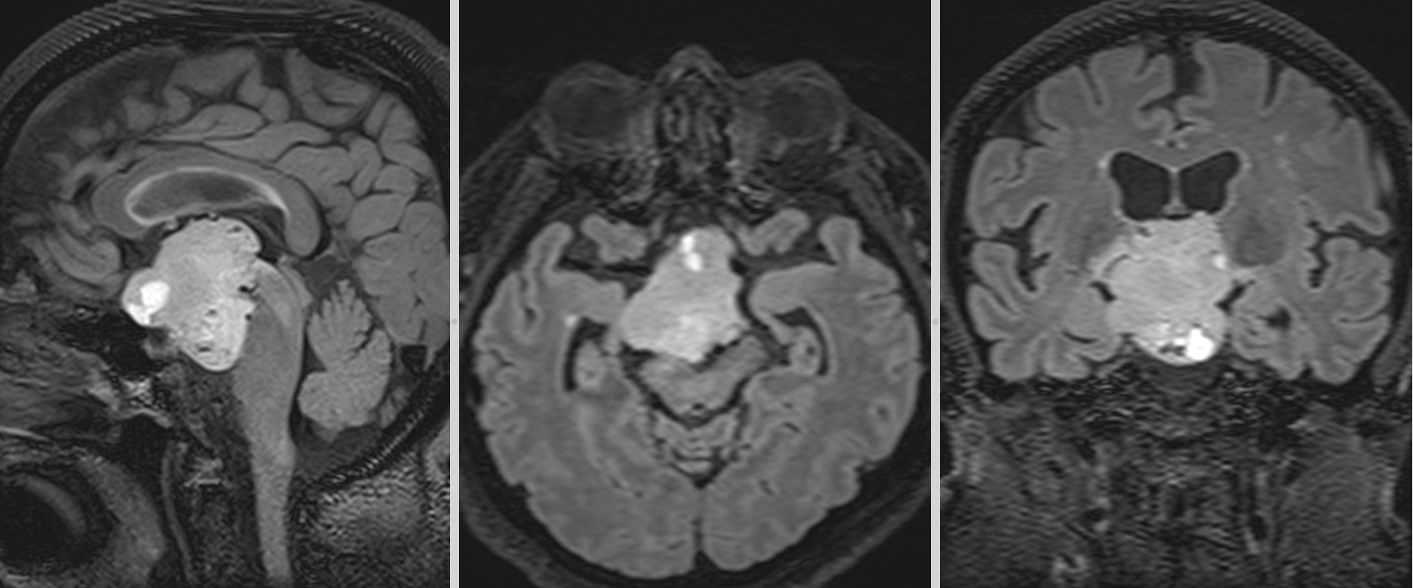

- Adamantinomatose: cele mai frecvente, întâlnite predominant la copii. Prezintă chisturi mari, calcificări extinse și un epiteliu scuamos, cu arii keratinoase (keratină lamelară) și colesterol în interiorul chisturilor.

Localizare și creștere tumorală

Craniofaringioamele au localizare predominant supraselară, dar pot avea extensii variabile în zona selară, hipotalamică, chiasmatică și ventriculară. Frecvent, tumora comprimă structurile din vecinătate, inclusiv hipotalamusul, hipofiza, chiasma optică, arterele cerebrale anterioare și ventriculii laterali. Această poziționare explică simptomatologia complexă, care poate include tulburări endocrine, neurologice și vizuale.

- Imagistica cerebrală (RMN și CT) este esențială. RMN-ul evidențiază tumora în detaliu, oferind informații despre extindere și relațiile cu structurile adiacente. CT-ul evidențiază mai bine calcificările caracteristice craniofaringioamelor adamantinomatose.